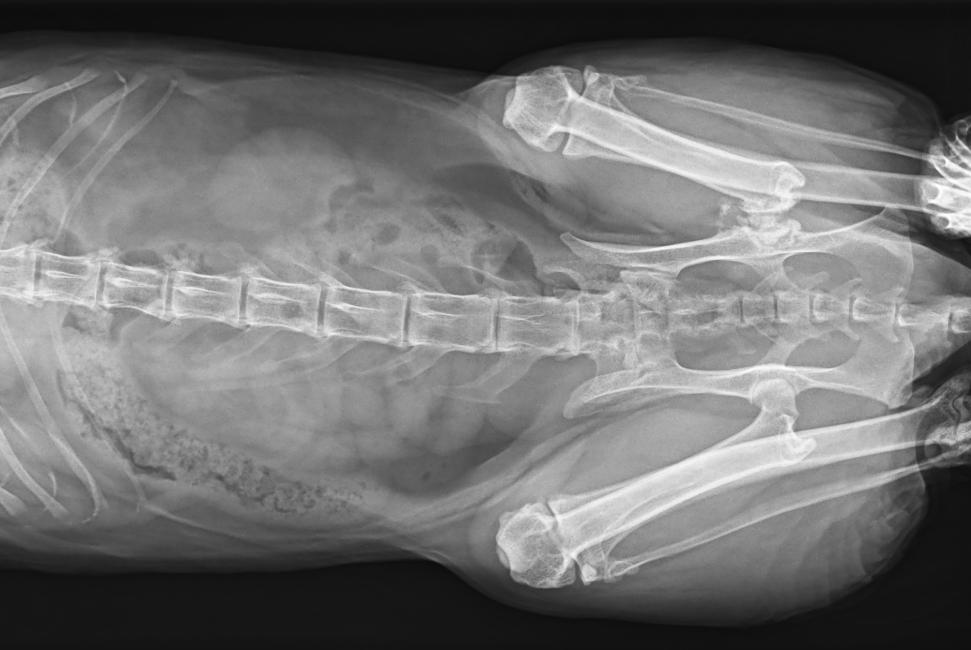

專為拍攝寵物設(shè)計(jì) VET1900 寵物DR

● 17*17大尺寸平板探測(cè)器,獲得高質(zhì)量圖像

● 優(yōu)異的空間分辨率及信噪比,提升圖像質(zhì)量

● 采用線噪聲消除技術(shù),使成像質(zhì)量提升40%

● 智能高效的圖像處理軟件,大幅提升圖像質(zhì)量